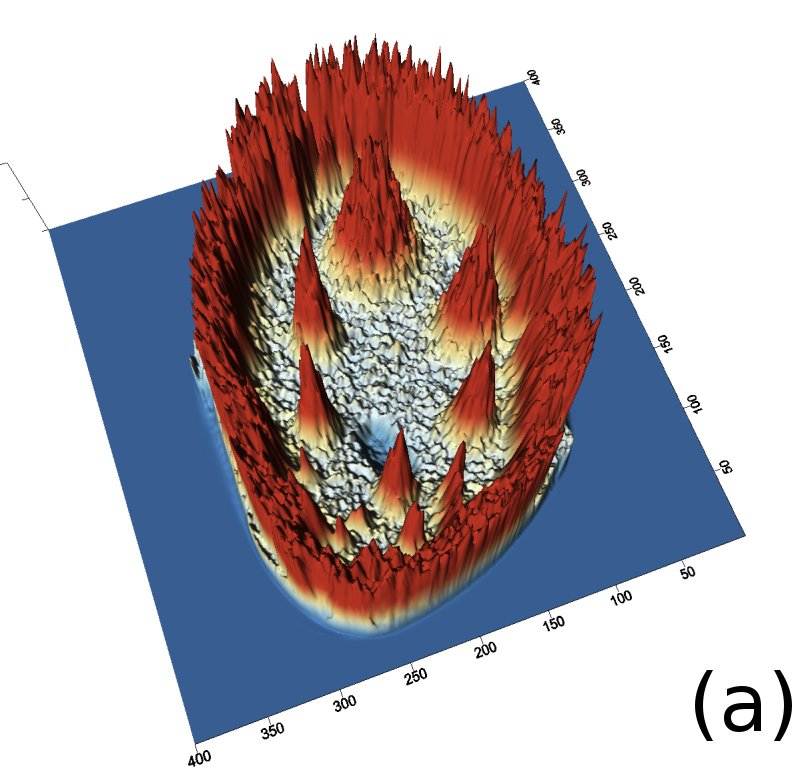

Reconstructed images are presented in Fig. 4. Since CGLS-TV- reconstruction might look more appealing than CGLS-EL we also show the surface representations of reconstructed images (see Fig. 5) and horizontal middle cross-sections (see Fig. 6).

One can notice that CGLS reconstruction is very noisy. CGLS-TV method better suppresses noise, however smooth features are strongly affected by the “staircasing” effect. CGLS-TV- method provides reconstruction with smoother features and CGLS-EL method resolves smooth features even better (e.g. cone-shaped parabola). Although CGLS-EL method performs very well for smooth objects one can notice the wave-like variations of intensity in the background and also at the top of the rectangle (see Fig. 6). This issue can be explained by the properties of our regularizer, in contrast to TV, our penalty does not seek the sparsest solution and does not penalize strongly (pushing to the constant value) a small intensity perturbations. The EL term tends to preserve all sharp edges while uniform noise is smoothed isotropically with the Laplacian. In Fig. 6 one can see that the CGLS-EL method provides better recovery of smooth features while slightly higher (compare to TV and TV-) perturbations visible in uniform areas (the top of the rectangle), however, the edges of the rectangle are defined sharper with the EL penalty.

In Fig. 10 and 11 one can notice that the BR is very smooth for TV and TV- penalties and some long-wave oscillations can be seen in the reconstructed image with EL penalty. This result corresponds to the expected behaviour of the EL penalty. We note here that the phantoms background (see Fig. 7) is not as flat as TV and TV- penalty recovered it. Furthermore, a small size dot-like feature (approximately in the centre of the phantom) is almost smoothed out with TV and TV- recovery. However, it is visible and well recovered with EL penalty. The sharp features, overall, are reconstructed very well with MLEM-EL method and seem even sharper compare to other methods (see the bone outer rim in Fig 10).